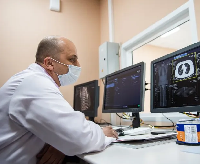

Магнитно-резонансная томография (МРТ):один из самых эффективных методов диагностики заболеваний